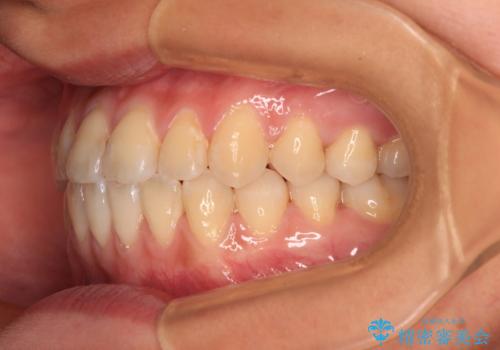

前歯のクロスバイトを治したい ワイヤー装置による矯正治療

クロスバイト改善まではスムーズに進みましたが、その後は強い舌の突出癖によりオープンバイトの期間が長く続きました。

舌のトレーニングをしっかりと実施してもらい、何とか仕上げることができました。